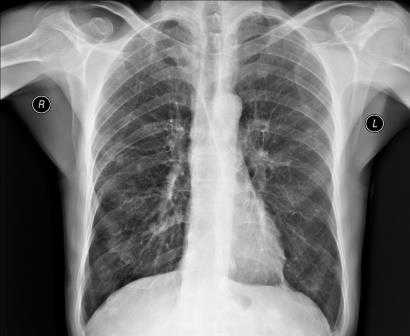

Для выявления патологических изменений сердца и оценки их влияния на сосудистое русло легких наиболее часто применяют рентгенографическое исследование грудной клетки, позволяющее получить изображение средостения, сердца и легких.

Снимки обычно делаются в заднепередней и левой боковой проекциях. В заднепередней проекции благодаря уменьшению расстояния между сердцем и рентгеновской пленкой изображение сердца получается более четким и менее искаженным, чем в переднезадней. У лежачего пациента можно воспользоваться передвижным рентгеновским аппаратом, но он позволяет делать снимки только в переднезадней проекции.

Нормальная картина

В норме на снимках, выполненных в заднепередней проекции, ширина грудной клетки по меньшей мере в 2 раза превышает поперечный размер сердца. В то же время в переднезадней проекции относительные размеры и положение сердца могут быть другими; возможно усиление тени сердца и дуги аорты. Когда исследование проводится с контрольной целью, рентгенограммы грудной клетки должны подтверждать правильное положение катетеров и водителей ритма.

Отклонение от нормы

Для диагностики заболеваний сердца необходимо оценивать рентгенограммы грудной клетки с учетом данных анамнеза, физикального обследования, ЭКГ и предыдущих рентгенологических исследований.

Изменение формы сердца обычно заключается в увеличении левого или правого желудочка, левого предсердия или даже нескольких полостей. При увеличении левого желудочка в заднепередней проекции левая граница сердца становится круглой и выпуклой с боковым расширением в своей нижней части, а в боковой проекции определяется выбухание левого желудочка кзади. При увеличении правого желудочка в заднепередней проекции наблюдается вторичное изменение левой границы сердца за счет расширения тени легочной артерии, а в боковой - расширение тени выносящего тракта правого желудочка. При увеличении левого предсердия его плотность на рентгенограмме в заднепередней проекции увеличивается вдвое, левая граница сердца сглаживается, левый главный бронх смещается кверху. В редких случаях правая граница сердца над проекцией правого желудочка расширяется кнаружи. В боковой проекции определяется выбухание левого предсердия кзади. Начальными признаками застоя в малом круге кровообращения на снимках, сделанных в заднепередней проекции, являются расширение тени легочных вен в верхнебоковой части корней легких и сосудистые тени, расположенные горизонтально вдоль нижней части правой границы сердца. Хроническая легочная венозная гипертензия приводит к формированию рисунка по типу оленьих рогов (из расширенных верхних и нормальных или суженных нижних легочных вен). При остром отеке легких увеличение плотности в центре легочных полей может по форме напоминать бабочку. Интерстициальный отек легких может напоминать снежные хлопья на фоне легочных полей.